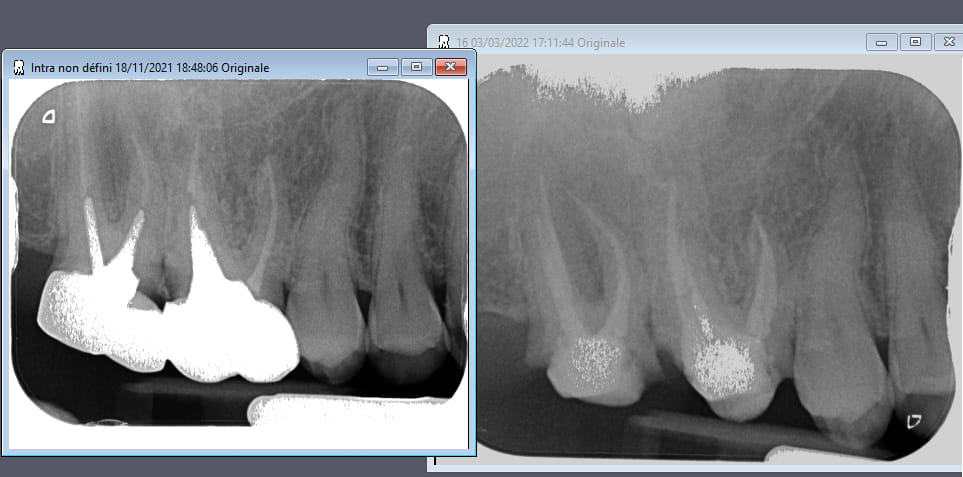

Je souhaiterais avoir votre avis concernant un patient de 40ans qui revient au cabinet 5 semaines après avoir dévitalisé sa 26 avec des douleurs qui s'accentuent depuis quelques jours.

A l'examen, rien de particulier à signaler. La dent est sensible à la percussion axiale et transversale.

J'ai refais une retroalveolaire et je trouve que ce n'est pas très nette au niveau de l'apex de la racine MV.

si c'etait le leger depassement sur la racine MV il aurait eu mal au bout de 3 jours .Il faudrait plutot penser a 1 MV2(deuxieme canal dans la racine MV)

J'ai cherché mais je n'en ai pas trouvé. Peut-être une bifurcation apicale ?